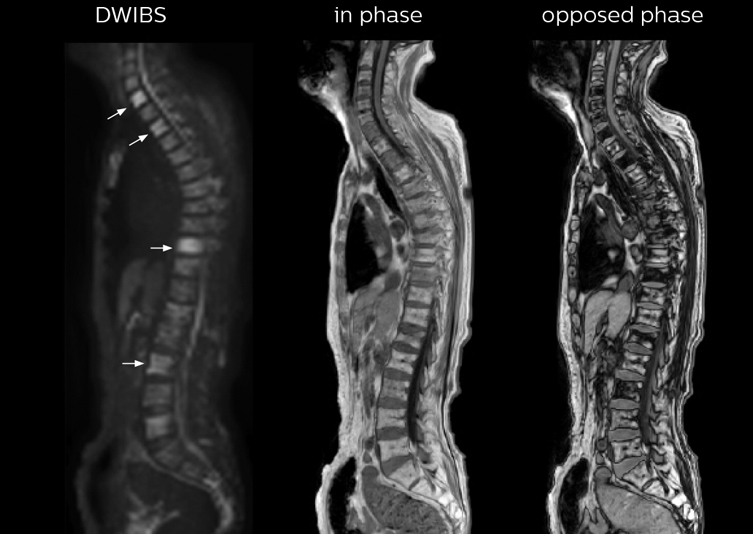

“When we limited the scan coverage to the area from neck to femur, we could fit more clinical information in approximately the same scan time. So, we added coronal mDIXON, sagittal T1-weighted, and sagittal STIR sequences to our examination, instead of performing only axial DWIBS and coronal single-shot TSE scans.”

The single shot T2-weighted TSE images are used for morphology and compared to DWIBS images to identify T2 shine-through. Sagittal STIR images are used in patients with inflammation or bone metastasis.

“In-phase and out-phase sagittal T1-weighted FFE images help us to visualize and further characterize bone lesions such as metastasis and bone-marrow hyperplasia that have high signal on DWI. These images are also used throughout radiotherapy, to monitor changes in the fatty bone marrow.”